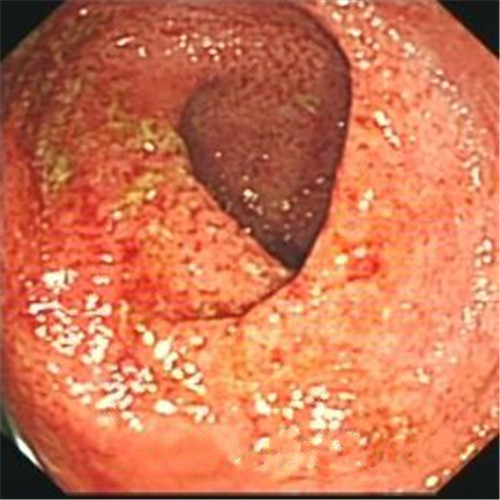

潰瘍性結腸炎圖片

潰瘍性結腸炎治療前後對比